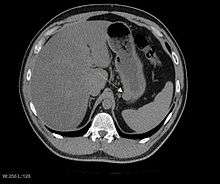

CT image of a GIST in the gastric cardia. The lesion appears submucosal, is hypervascular and protrudes intraluminally. Upper GI bleeding led to endoscopy, finding an ulcerated mass.

Non-enhanced CT image of a small GIST in the posterior stomach wall (arrow). The lesion appears subserosal. Incidental finding.

As the tumor grows it may project outside the bowel (exophytic growth) and/or inside the bowel (intraluminal growth), but they most commonly grow exophytically such that the bulk of the tumor projects into the abdominal cavity. If the tumor outstrips its blood supply, it can necrose internally, creating a central fluid-filled cavity with hemorrhage and cavitations that can eventually ulcerate and communicate into the lumen of the bowel. In that case, barium swallow may show an air, air-fluid levels or oral contrast media accumulation within these areas.[16][17] Mucosal ulcerations may also be present. In contrast enhanced CT images, large GISTs appear as heterogeneous masses due to areas of living tumor cells surrounding hemorrhage, necrosis or cysts, which is radiographically seen as a peripheral enhancement pattern with a low attenuation center.[15] In MRI studies, the degree of necrosis and hemorrhage affects the signal intensity pattern. Areas of hemorrhage within the tumor will vary its signal intensity depending on how long ago the hemorrhage occurred. The solid portions of the tumor are typically low signal intensity on T1-weighted images, are high signal intensity on T2-weighted images and enhance after administration of gadolinium. Signal-intensity voids are present if there is gas within areas of necrotic tumor.[18][19][20]

Malignancy is characterized by local invasion and metastases, usually to the liver, omentum and peritoneum. However, cases of metastases to bone, pleura, lungs and retroperitoneum have been seen. In distinction to gastric adenocarcinoma or gastric/small bowel lymphoma, malignant lymphadenopathy (swollen lymph nodes) is uncommon (<10%) and thus imaging usually shows absence of lymph node enlargement.[15] If metastases are not present, other radiologic features suggesting malignancy include: size (>5 cm), heterogeneous enhancement after contrast administration and ulcerations.[3][15][21] Also, overtly malignant behavior (in distinction to malignant potential of lesser degree) is less commonly seen in gastric tumors, with a ratio of behaviorally benign to overtly malignant of 3-5:1.[3] Even if radiographic malignant features are present, these findings may also represent other tumors and definitive diagnosis must be made immunochemically.